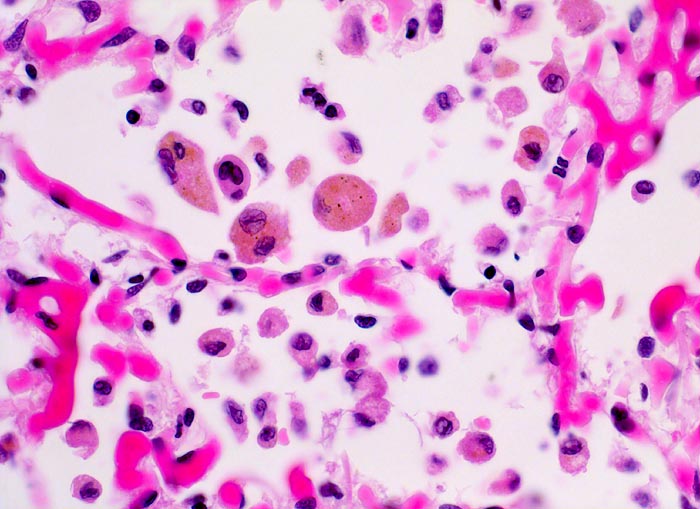

In einer frühen Phase kommt es zur roten Stauungsinduration, welche in eine braune Stauungsinduration übergeht. Die Eindrückbarkeit der Lungen ist aufgrund der Fibrosierung der Alveolarsepten vermindert. Die meist fleckförmige braune Verfärbung beruht auf der Anhäufung von hämosiderinhaltigen Herzfehlerzellen in den Alveolarlichtungen. Makrophagen in den Alveolarlichtungen phagozytieren die ausgetretenen Erythrozyten. Der Nachweis von Erythrozyten im Zytoplasma von Makrophagen spricht für eine frische Blutung. Nach 3-5 Tagen ist in den Makrophagen Hämosiderin nachweisbar. Das Hämosiderin lässt sich mittels Eisenfärbung (Berliner-Blau) zuverlässig von Staubpigment abgrenzen. Als sicheres Zeichen für eine ältere Blutung gelten >20% hämosiderinspeichernde Makrophagen in der bronchoalveolären Lavage (BAL). Die hämosiderinhaltigen Alveolarmakrophagen werden auch Herzfehlerzellen genannt, da sie gehäuft im Rahmen einer linkskardialen Stauung bei Mitralklappenstenose auftreten.

• Mediahypertrophie der Pulmonalvenen.

• Fibrosierung und Verdickung der Alveolarsepten.

• Siderinhaltige Alveolarmakrophagen (=Herzfehlerzellen).